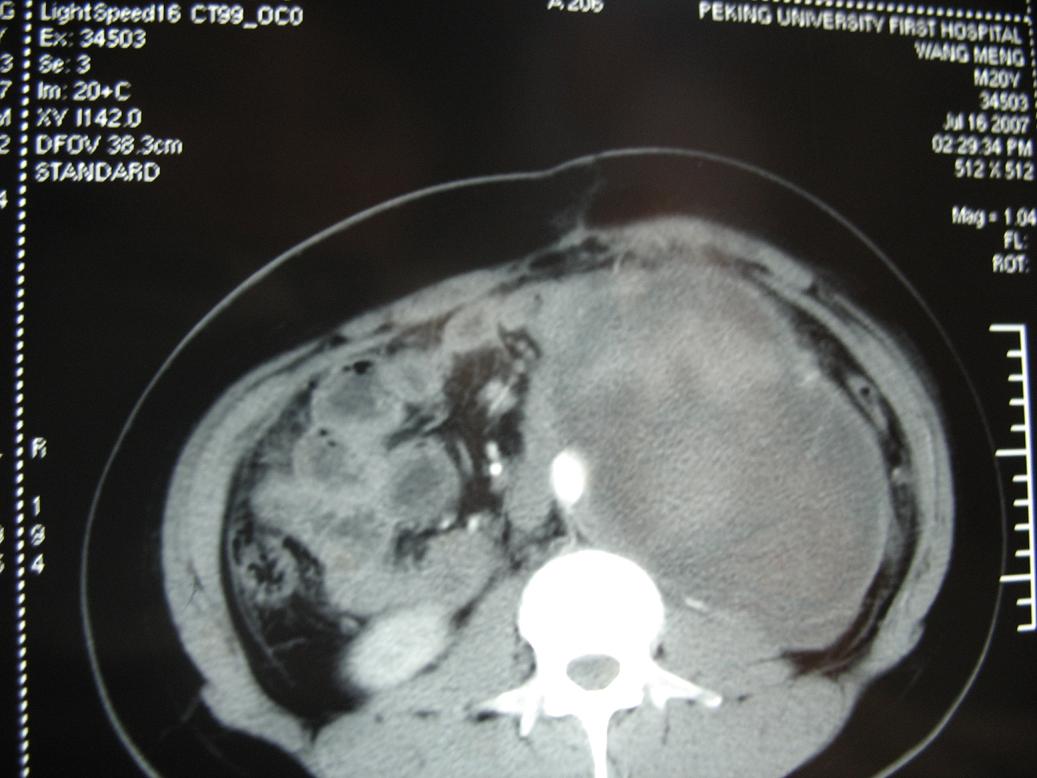

m20,发现腹部肿物二月.

无肠梗阻及主动脉受压向前右移位,应该定位于腹膜后肿瘤,囊实性密度,内可见点状钙化影,及出血征象,患者年龄轻,考虑畸胎瘤或生殖细胸胞瘤可能性大.蒙一下.

2、左侧腹膜后囊实性占位性病变,有完整包膜,周围脏器及血管呈受压移位改变,左肾积水,肾实质变薄,增强扫描示病变包膜有强化,因图片太少,实性部分是否强化不好判断。

3、诊断:结合病人年龄,左肾改变考肿虑为输尿管受压肾积水时间长,左肾实质萎缩,病变未见明显外侵征象,本人首先考虑为神经源性瘤囊变可能性大。

考虑腹后肿瘤,肿瘤前缘与左腹直肌有条状影相连,且左腹直肌和相邻腹膜稍厚,腹主动脉有被包绕改变,提示恶变的可能。

结果收到,肿块较大,密度不均,实性部分有强化,包绕腹主动脉推挤左肾,左肾集合系统受压改变,病灶长轴与腹主动脉平行,支持副神经节瘤,但不典型。